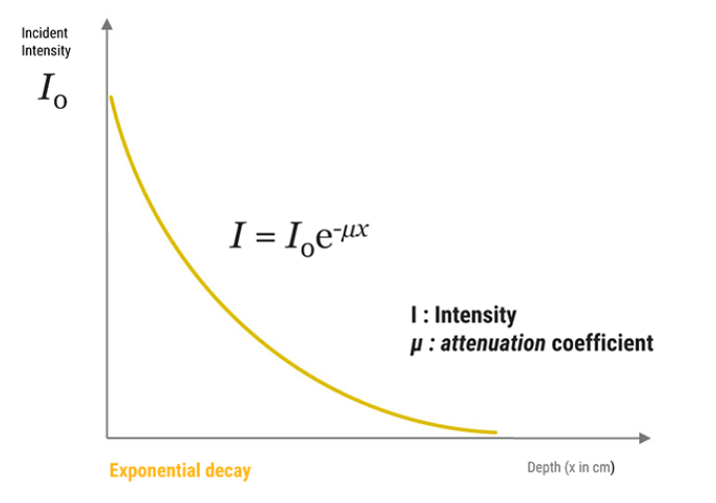

Global Attenuation

The amplitude and intensity of ultrasound waves decrease as they travel through tissues. Theoretically, the attenuation coefficient (μ) in soft tissues, is almost proportional to the ultrasound frequency and depth, with a range between 0.5 and 1 dB / (MHz.cm).

The attenuation is one of the parameters that limit the maximum frequency. It is important to note that lowering the frequency improves the depth of exploration because the ultrasound attenuation primarily increases with frequency. The maximum depth of exploration with a center frequency of 20 MHz is approximately 6-10 mm.

The sound energy is attenuated or weakened as it passes through the tissues. In fact, as the ultrasound wave travels through a medium, parts of it are reflected, scattered, absorbed or refracted.

Absorption

As discussed previously, the absorption is the reduction in the intensity of the sound waves as it passes through a tissue. Most of the energy loss is in the form of heat. The absorption of the sound energy in tissues largely contributes to its overall attenuation, where the degree of attenuation depends on the biological tissue, and the frequency of the wave. The degree of soft tissue attenuation follows an almost linear relationship with the frequency.

- The higher the frequency, the greater the attenuation

- As the attenuation increases, the depth of exploration decreases

The ultrasonic energy is attenuated exponentially while the wave passes through the tissues. We can conclude that the ultrasound wave is strongly attenuated by the bones than other organs.